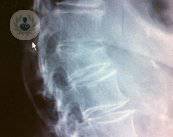

¿Qué es un aplastamiento vertebral?

Con más de 30 años de experiencia en la especialidad de cirugía de columna, el Dr. Pérez-Hickman nos habla a cerca de los tratamientos para combatir un aplastamiento vertebral. La cifoplastia es una de las técnicas más eficaces y mínimamente invasivas.